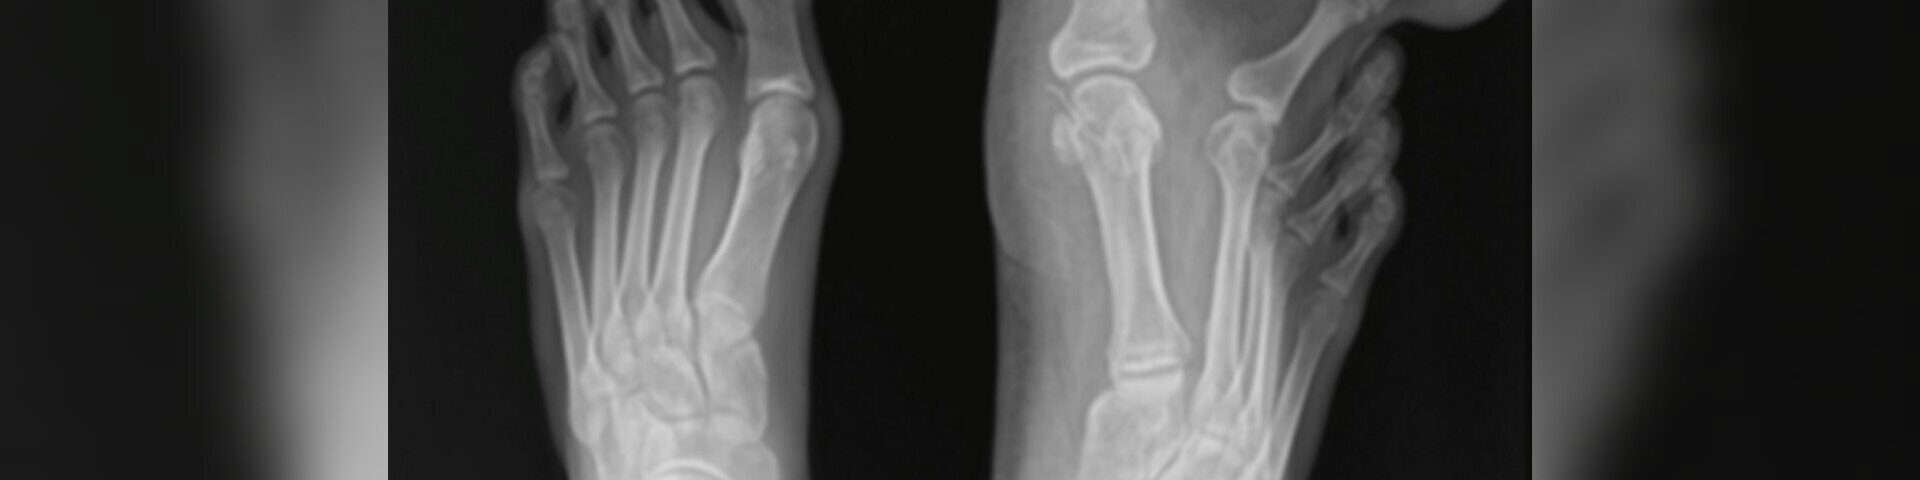

Uma garota de 12 anos foi operada na Malásia para retirar e remodelar parte de seu dedão e do segundo dedo do pé. Ela tinha uma rara má-formação congênita conhecida como macrodistrofia lipomatosa, que leva ao crescimento desproporcional dos dedos das mãos e/ou dos pés.

A condição é rara e atinge especialmente os membros inferiores, de acordo com relato de caso publicado na revista Cureus em agosto de 2023. Responsáveis pela operação da menina, os ortopedistas da Universiti Kebangsaan contaram que ela quase não usava sapatos por causa do extremo desconforto.

Segundo o texto, a menina apresentou o problema desde o nascimento. Apesar de benigna, a doença prejudicava seu equilíbrio e mobilidade, além de afetar a autoestima dela. No entanto, os pais esperaram até os 12 anos para decidir pela operação.

A equipe optou por uma cirurgia de reconstrução dos dedos para tirar o excesso de tecido adiposo e também retirou uma das falanges dos pés. “Como resultado da cirurgia, ela agora pode usar sapatos sem dificuldades”, diz o texto dos médicos.